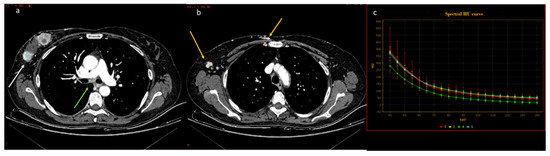

| Wang et al. [56] Retrospective study | China | To objectively and subjectively assess and compare the characteristics of mono-energetic images and poly-energetic images acquired by DECT of patients with breast cancer | 42 | SOMATOM Drive, Siemens Healthineers No C.I. | Reconstructions at low keV in the venous phase acquired by DECT improved the objective and subjective assessment of lesion conspicuity in patients with malignant breast lesions. |

| Volterrani et al. [57] Retrospective study | Italy | To demonstrate the feasibility of DECT for locoregional staging of breast cancer and differentiation of tumor histotypes | 31 | Discovery CT 750 HD, GE Healthcare No C.I. | DECT is feasible and seems to be a reliable tool for locoregional staging of breast cancer. |

| Moon et al. [58] Retrospective study | South Korea | To evaluate the predictive value of VMI by assessing tumor conspicuity on dual-layer spectral detector CT and correlate tumor conspicuity on VMI with prognostic biomarkers in patients with breast cancer | 64 | IQon Spectral CT, Philips Health System No C.I. | VMI40DEL may be useful in the diagnosis of breast cancers due to higher tumor conspicuity and better enhancement than VMI40ART. VMI40ART may be beneficial for the prediction of poor breast cancer prognoses. |